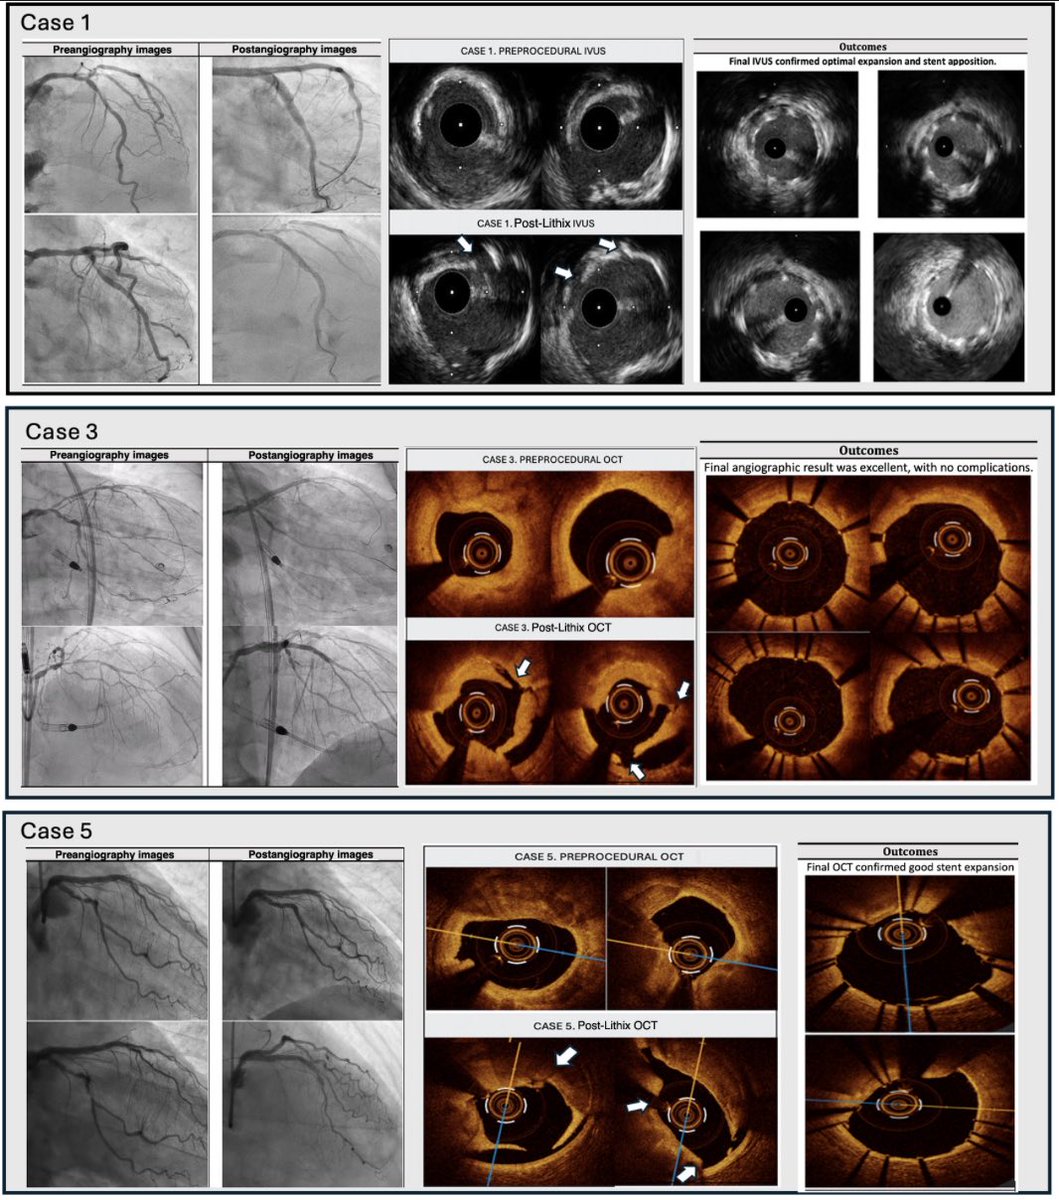

Read here our initial experience with the Lithix litothrypsy balloon 👉 https://t.co/bgaTiy4j46 @ElenaIzaga @JuradoRomanAl @NachoGalloFer @AsanperHVS @shci_sec @PCRonline @marcelordgzm

33

🤓Read our last investigation regarding the new LithiX lithotripsy system for the treatment of severe coronary calcification: early real-world experience 👉 https://t.co/rYynfPzrVb @ElenaIzaga @JuradoRomanAl @MPAOSS @AsanperHVS @RevEspCardiol @PCRonline

54